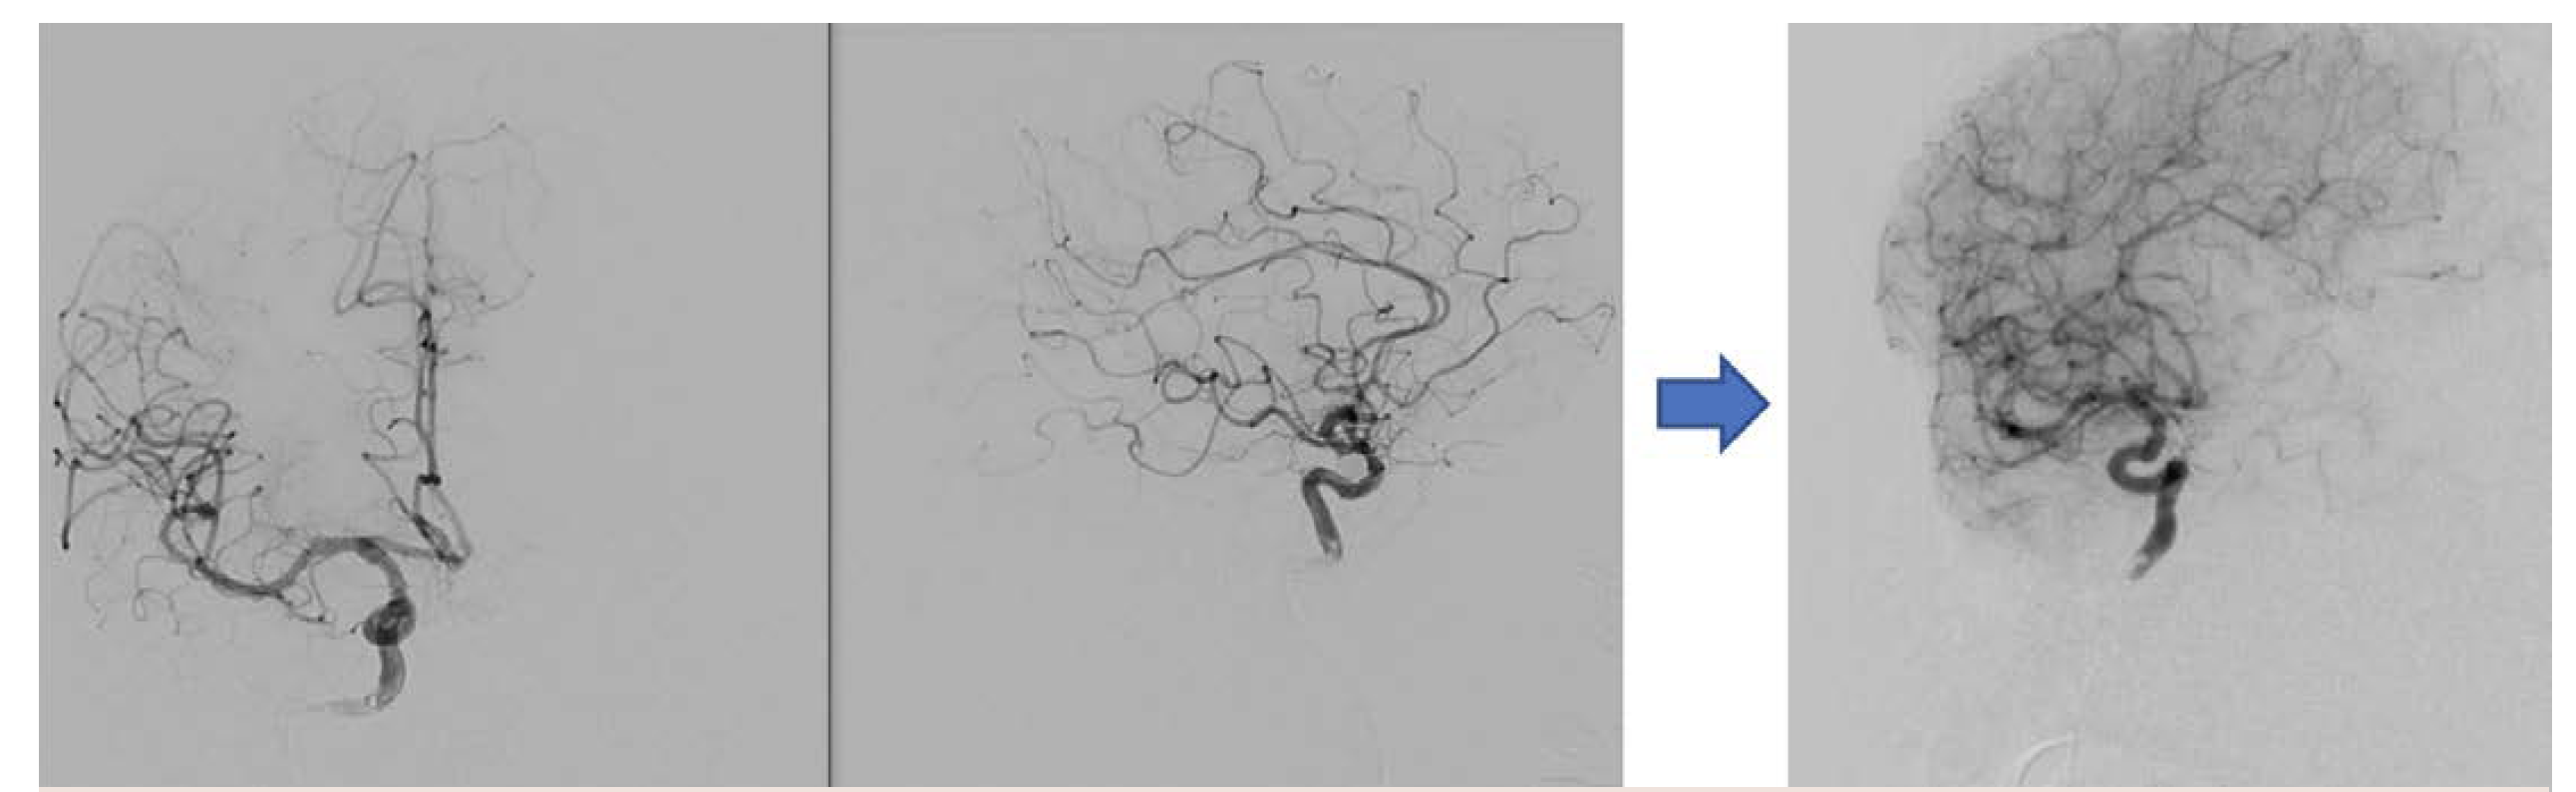

In this case, a healthy 62-year-old presented with a partially thrombosed giant vertebrobasilar junction and midbasilar aneurysm (Figure 10).

Imaging was performed with a 4-second DSA 3D acquisition with simultaneous injection in both vertebral arteries, power-injected on the left and hand-injected on the right (Figure 11). The plan based on these images was to flow divert from the left vertebral artery into the distal basilar artery and coil the distal right vertebral artery. Originally, the plan was to embolize the right vertebral artery distal to the posterior inferior cerebellar artery (PICA) origin. However, this plan changed based on findings from the right vertebral injection—findings that were dependent on the resolution of the imaging.

After a 3-stent construct was built, a DynaCT Micro with contrast was obtained, which demonstrated excellent stent-stent and stent-wall apposition (Figure 15). Even more important, it resolved an entire collateral arcade, replacing the native basilar artery and extending from the distal left vertebral artery (no stent covering the origin) to the distal basilar artery (1-stent coverage). This anatomic resolution enabled a more aggressive approach to the aneurysm neck, and ultimately 6 stents were placed. This anatomic collateral has previously been theorized and assumed to occur in the setting of giant midbasilar aneurysms without infarct. However, with DynaCT Micro, it can actually be visualized.

The original plan was to coil off the right vertebral artery distal to PICA. However, the imaging resolution of the ARTIS icono enabled visualization of critical medullary perforators distal to the PICA origin (Figure 16). The plan was therefore modified to coil off the vertebral distal to the most distal of these perforators. The distal right vertebral artery was successfully embolized distal to the perforators (Figure 17).

The patient returned for a 6-month follow-up angiography. Anterior-posterior, lateral, and 3D dual volume imaging was done at 6 months (Figure 18). Note the calcified shell of the aneurysm on the 3D image. The patient was neurologically normal and returned to work as well as running multiple times per week.